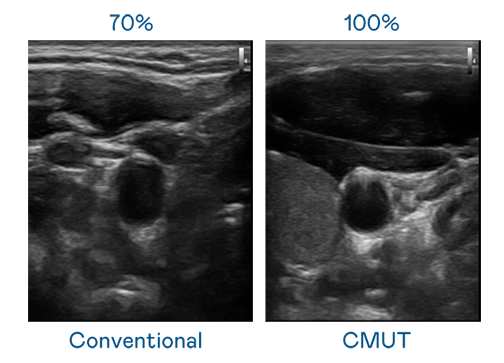

CMUT 技术是一种用电容式微机电元件来产生超音波讯号的技术。与传统 PZT 压电式技术相比,CMUT 频宽增加 30%,更宽频的超音波讯号让影像解析度大幅提升,是实现高影像品质医疗超音波扫描、促进精准医疗发展的关键技术。

大频宽带来超清晰影像

超音波影像的解析度高低,首先取决于探头能发出的讯号频宽。z6尊龙时凯 CMUT 可提供高清晰的超音波讯号,提供高频宽、高灵敏度、影像纹理细节更高的超音波影像,协助医护人员缩短影像判读时间及利用精准的医疗影像进行诊断。